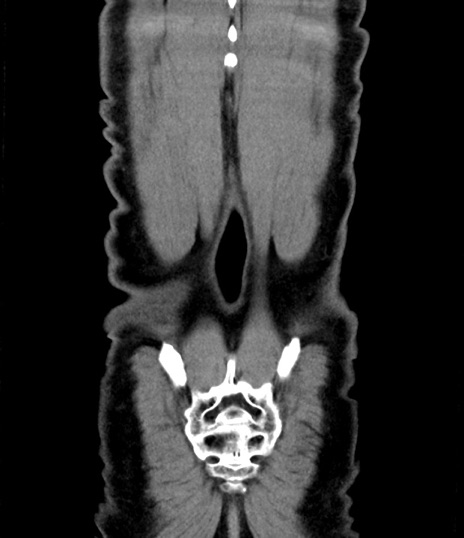

症例8(冠状断像)

【症例】 60歳代男性

【主訴】 黒色吐物

【現病歴】 4日前から嘔気自覚、2日前の朝食後にも嘔気あり、自分で手で嘔吐反射起こし嘔吐したところ血が混ざっていたため受診。

【既往歴】 5年前汎発性腹膜炎を伴う急性虫垂炎で手術、高血圧、前立腺肥大症、高脂血症

【身体所見】 腹部正中に手術癩痕あり 腹部平坦・軟圧痛なし膨満感あり

【データ】WBC 8400、CRP 4.54